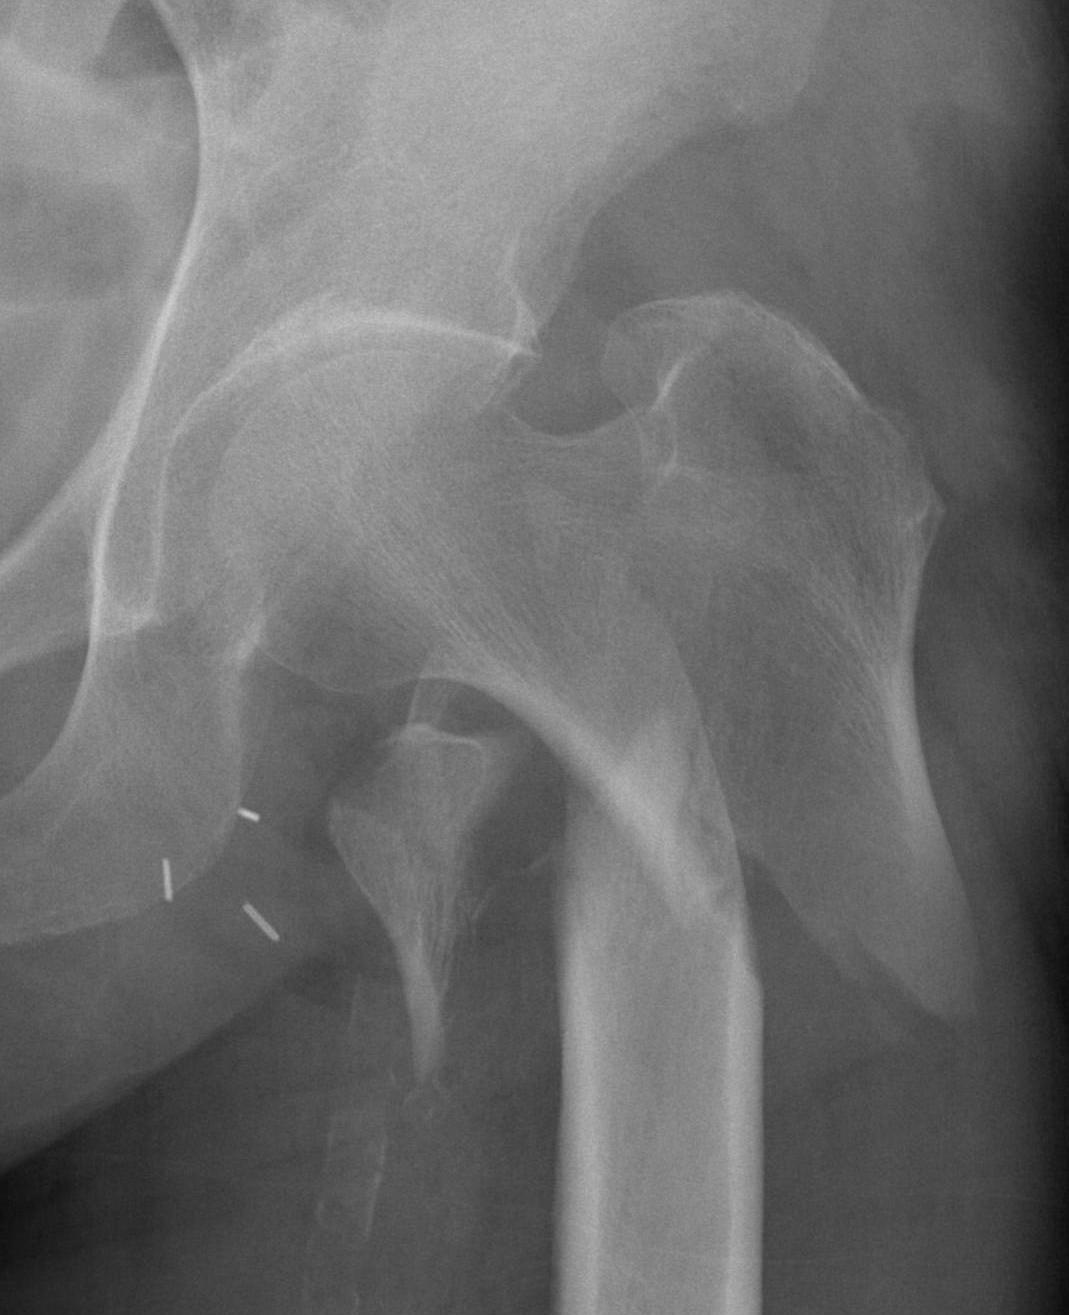

Dynamic hip screw

Mechanism

Plate is a lateral tension band whilst the sliding screw allows controlled fracture impaction

Technique

Guide wire

- centred in femoral head in 2 planes

- tip-apex distance < 25 mm

Tip - apex distance

- from tip of screw to apex femoral head

- accumulative on AP and lateral

- > 25 mm, increases cut out